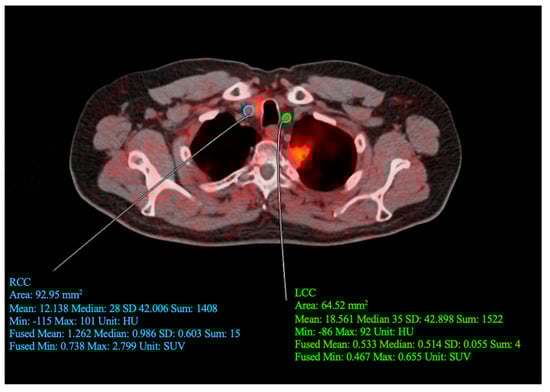

To assess inflammation and microcalcification as FDG and NaF uptake, respectively, we employed OsiriX MD software v.13.0.1 (Pixmeo SARL, Bernex, Switzerland), a DICOM viewer and image-analysis program. On the fused FDG- and NaF-PET/CT images, regions of interest (ROIs) were delineated around the carotid artery wall (Figure 1). The entire common carotid structure was segmented, extending from the origin of the aortic arch (on the left) or the brachiocephalic trunk (on the right), to the point of carotid bifurcation (at the level of the fourth cervical vertebra or the laryngeal prominence). The mean standardized uptake value (SUVmean) was determined for each region of interest by averaging the values of all voxels contained with the defined boundaries.

Figure 1.

Quantitative assessment conducted by defining regions of interest (ROI) around the left (LCC) and right (RCC) common carotid arteries. For the drawn RCC ROI, SUVmean = 1.262, SUVmin = 0.0738, and SUVmax = 2.799. For the drawn LCC ROI, SUVmean = 0.533, SUVmin = 0.467, and SUVmax = 0.655.

NaF-PET/CT imaging demonstrated elevated NaF uptake in the bilateral carotid arteries, with an average SUVmean of 1.12 for both right and left carotids. This yielded a z-score of 0.012 when compared to a cohort of 38 patients with elevated cardiovascular risk. Conversely, FDG-PET/CT imaging revealed low FDG uptake in the carotid arteries, with an average SUVmean of 0.66 for both right and left carotids and a z-score of −2.32.